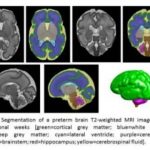

Study: Early lipids boost brain growth for vulnerable micro-preemies — (Details)

Dietary lipids, already an important source of energy for tiny preemies, also provide a much-needed brain boost by significantly increasing global brain volume...